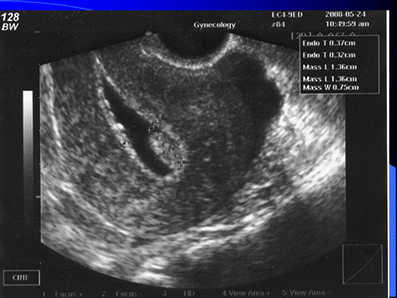

You may have light bleeding immediately after a uterine polyp removal. After an A D&C can be performed for a variety of reasons, usually to diagnose and treat various conditions of the uterus.

Weve made it simple for you to schedule an appointment right away via Whatsapp. or Healthwise, Incorporated disclaims any warranty or liability for your use of this information. This helps to prevent infection. It offers current information and opinions related to women's health. I havnt had sex since January 2016. discharge yellow dying tmi warning babycenter outcome bfp luck else anyone im experience I had a hysterectomy on Feb 10th. Today I called my Dr. It includes uterine bleeding, risk of infection, and pelvic inflammatory disease (PID).

You will probably be able to return to work the day after the procedure. hysteroscopy reliability abnormal uterine They left my cervix, why I have zero idea. Are you on any blood-thinning medication? Diagnosed Lupus and Chrohns and Hoping you still see this and have answers. But, wait until the next day to take a bath. Is this all normal what do I do. A D&C procedure, short for dilation and curettage, is typically performed by an OBGYN to remove tissue from inside the uterus. I havent really noticed much of a mini period this years, with the exception of a few. Fallopian Tubes: Tubes through which an egg travels from the ovary to the uterus. If youre having the procedure with general anesthesia, an anesthesiologist will give you an intravenous medication or a medication that youll inhale. Hi Angela I hope everything is going okay I was just wondering what happened if you got to see a doctor or not and if so what did you find out Im having some very similar problems and I am really needing some advice if you get a chance I would love to hear back from you thank you. Surgery and prescription medication dont always have to be your first plan to treat uterine fibroids. So I had a miscarriage at the end of January. They removed my cervix, sutures and mesh around cervix (which I didnt know I had). Give it time, dont push it give your body time to heal we get 1 chance of healing properly. | Vagina: A tube-like structure surrounded by muscles. We explain what you may expect to pay, how to enroll, and important deadlines. You may have some light vaginal bleeding. If your menstrual period is consistently longer or heavier than normal, your doctor may recommend endometrial ablation. What Every Woman Must Know, 5 Main causes of bowel problems after hysterectomy, Pain After Hysterectomy- Tips To Identify Its Source, 7 Ways to fight extreme fatigue after hysterectomy, A Hysterectomy Incision Sucks. What were your results? Complications from a D&C hysteroscopy are rare, but unfortunately do occur. Trauma or infection of the vagina can also cause bleeding. (2018). I bled for 2 weeks and then had 2 weeks without bleeding. There are many natural treatments for fibroids, To end fibroid pain, this writer decided to get a hysterectomy at age 41. But, if general anaesthesia was administered, it is best to snack on light meals. In the case of wound infection, antibiotics are the line of treatment. Ive definitely not taken it easy enough. Blood continues to be bright red. If your stomach is upset, try bland, low-fat foods like plain rice, broiled chicken, toast, and yogurt. If theydiscover the problem early, bleeding after hysterectomy is easier to manage and treat. WebHysteroscopy is a very safe procedure.